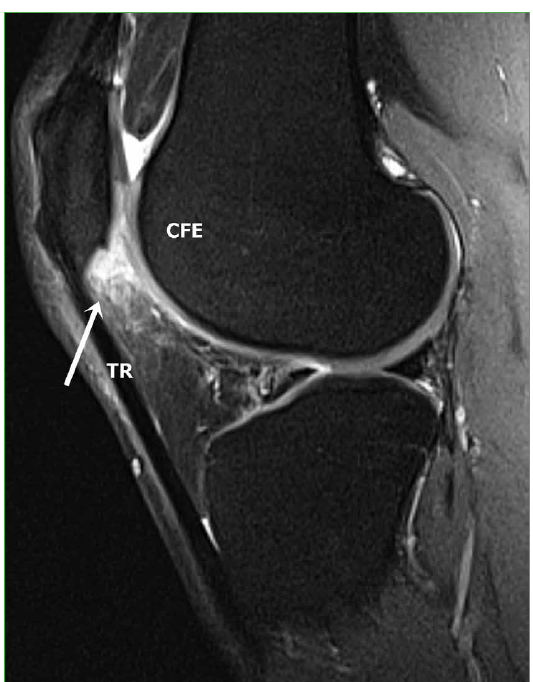

Figura 3.

Resonancia magnética, plano sagital, con secuencia densidad protónica con supresión grasa, consecutiva y lateral a la Figura 2. Se observa, con mayor intensidad, la señal a medida que nos desplazamos hacia lateral (flecha). Corresponde a edema entre el tendón rotuliano (TR) y la cara anterior del cóndilo femoral externo (CFE).